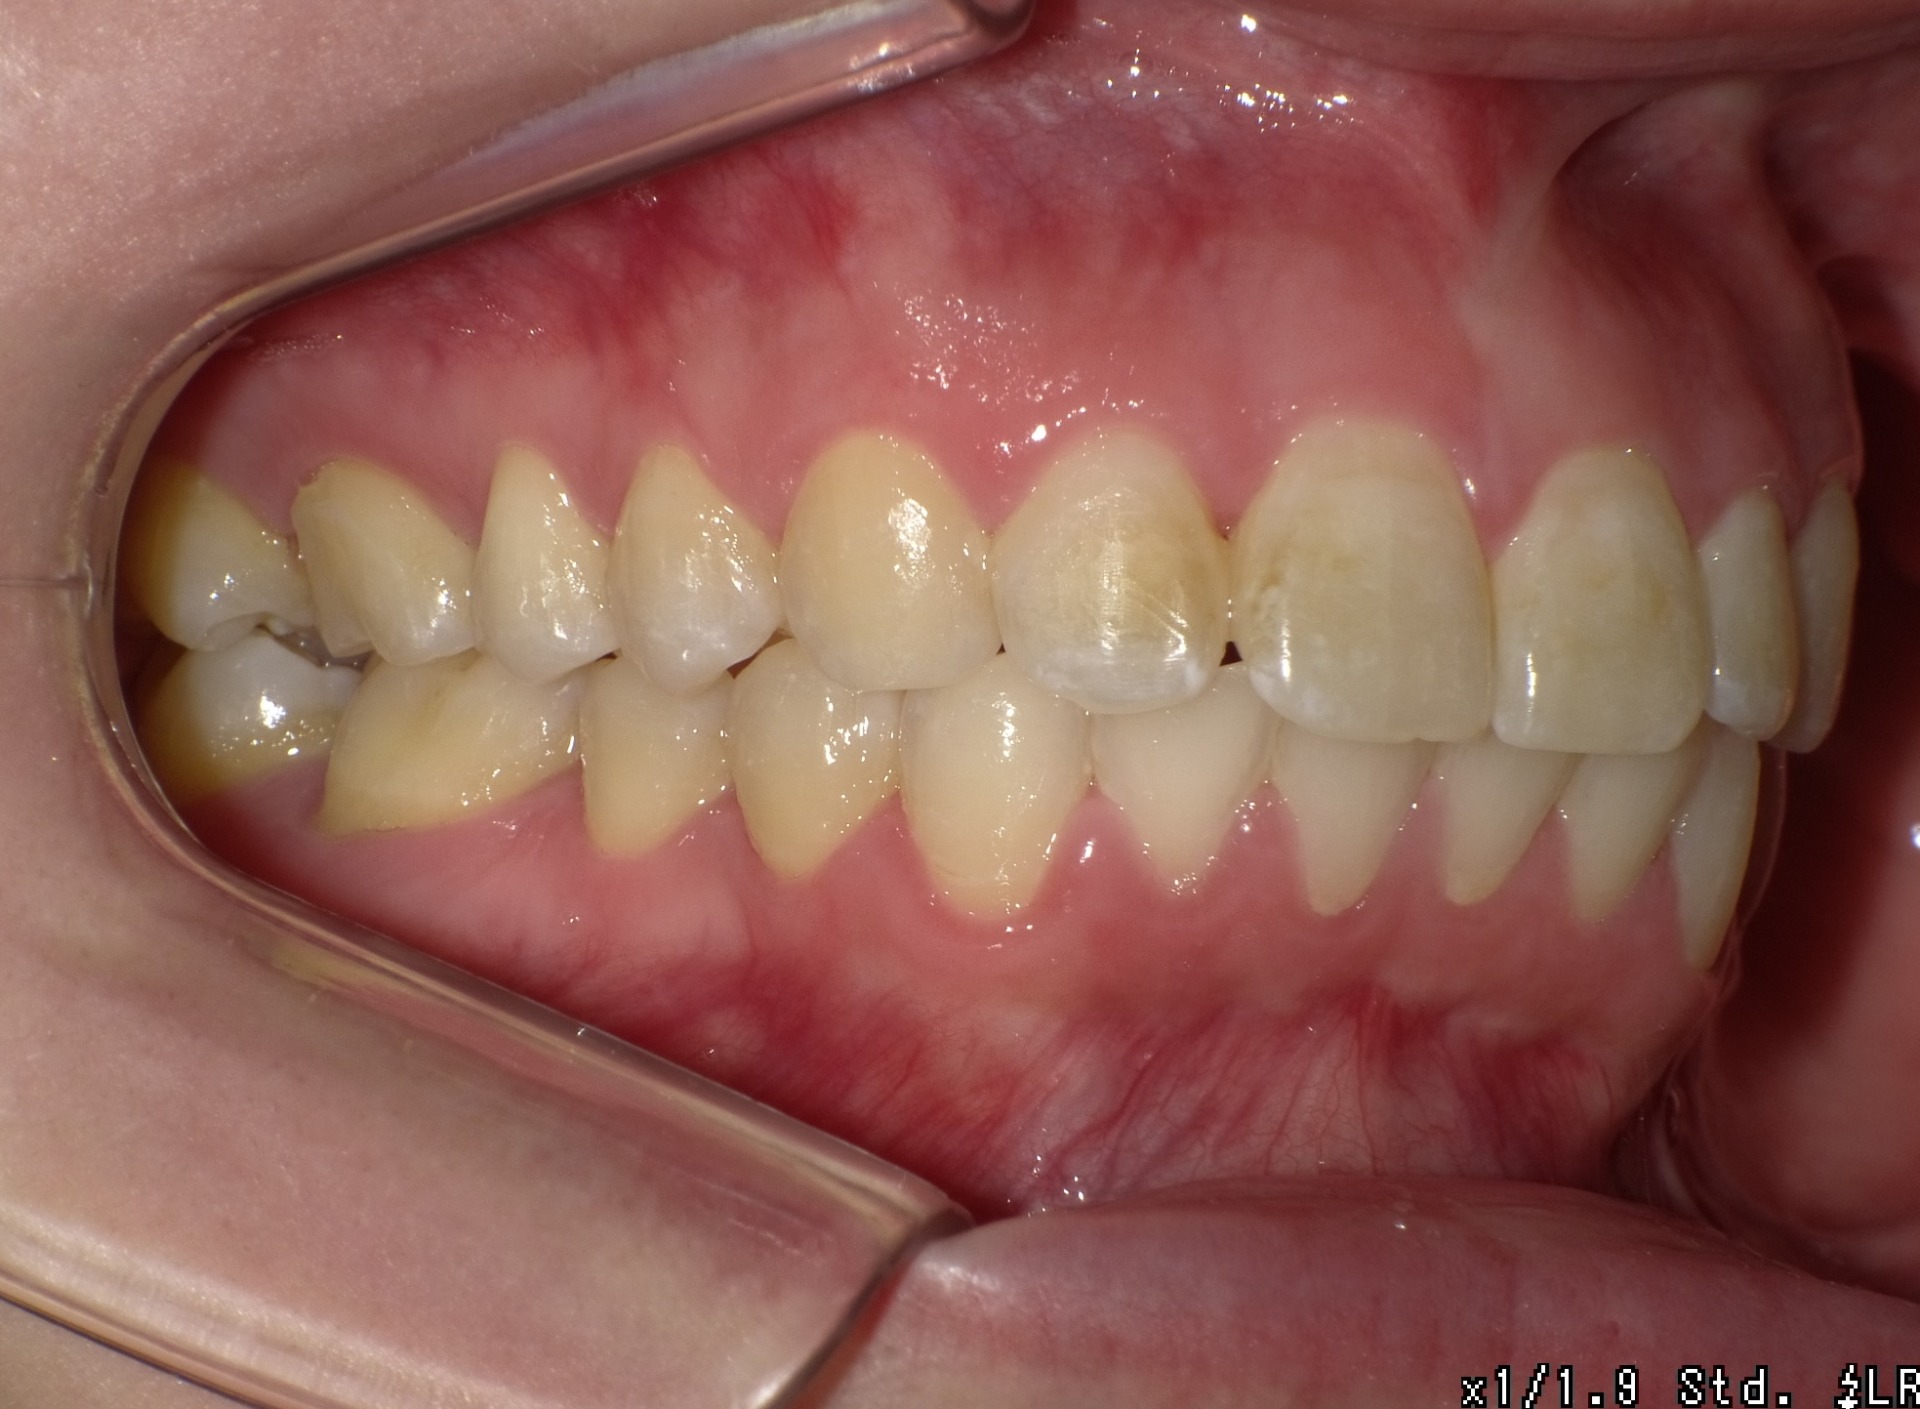

After

| 症状 | 前歯が出ている |

| 通院目的 | 永久歯を抜かずに歯並びを治したい。 |

| 処置内容 | ディスタライザー・マルチブラケット装置 |

| デメリット・院長コメント | 永久歯を抜かない治療のデメリットは、治療期間が長いことです。 ただし、その後の人生の長さを考えると、健全な小臼歯を2本または4本抜歯の矯正治療よりも、はるかにメリットがあるといえます。 また、アーチが小さくならないので、舌が後ろに押し込まれないためいびき防止につながり睡眠の質の向上にもつながります。 |